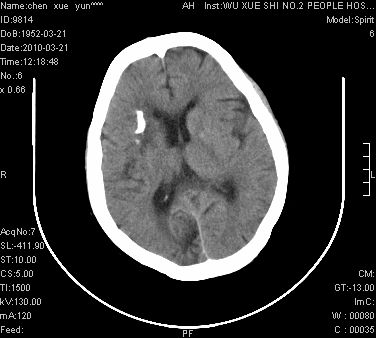

性别:不详;年龄:58岁;病史:不详。

ct表现:1、右侧额颞叶深部不规则钙化密度团块,呈弯曲条带状,占位效应不明显,考虑少枝胶质细胞瘤可能性大于血管瘤。2、右枕叶大片不规则低密度影,密度近似于脑脊液,右侧侧脑室后角及三角区扩张,考虑为陈旧性脑梗塞。

讨论:1、这个病灶的钙化有点像脑回样钙化,因此我最初考虑颅面血管瘤病(sturge-weber综合征),但是查阅了我们网站上的几个颅面血管瘤病病例,钙化均位于脑实质表面,沿脑回分布,而这例病灶位置较深,因此可以否定“颅面血管瘤病”这个诊断。

2、卜一会员曾经说过:少枝胶质细胞瘤的典型征象为弯曲条带状钙化,可作为定性的可靠征象(http://www.radida.com/news_view.asp?id=5150)

3、血管瘤也可以出现弯曲条带状钙化,但血管瘤多数出现“负占位”效应,即病灶周围的脑室、脑池及脑沟不是受压变窄,而是局限性的增宽。